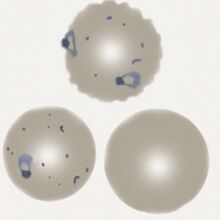

The late trophozoite

The later growth stage of trophozoites where parasites modification of the erythrocyte is seen with characteristic added dots and possible minor changes to red cell form:

- Parasites resemble early ring forms, but are thicker and may be slightly larger

- Additional blue/grey dots and clefts are seen in red cell cytoplasm when stained correctly

- These dots have low number a characteristic "dot" or "line" form Maurer's dots and clefts

- Size and shape of infected red cells is usually unaffected, but may become crenated

- The double dot, accolé, and multiple parasite forms remain present

P.falciparum late trophozoites